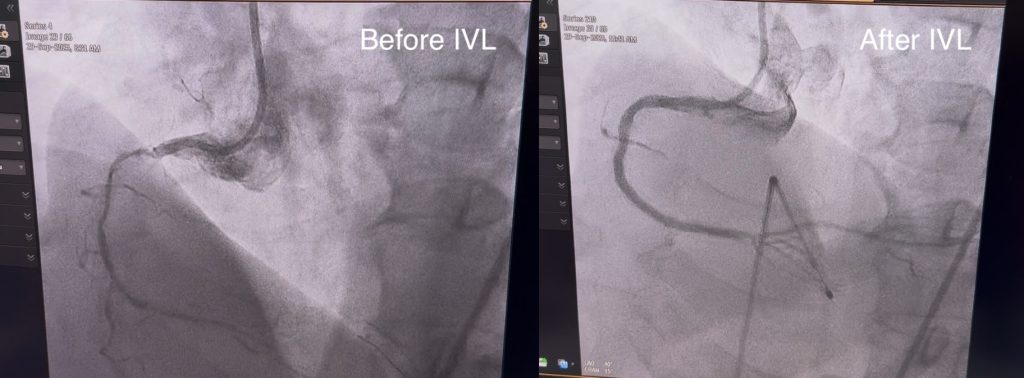

We present a case of intravascular lithotripsy (IVL) in a 63-year-old male patient. The patient presented with a CTO on the RCA (1VD CAD). A 3.00mm IVL catheter was used, delivering a total of 120 pulses throughout the RCA. The procedure was performed by dr. Amir Aziz Alkatiri, Sp.JP (K), FIHA at RSJPD Harapan Kita. The treatment resulted in a significant reduction in stenosis levels of the RCA. Additional stent implementation across three lesions sites were utilized. This case highlights the role of IVL in managing complex calcified vascular lesions.

A 63-year-old male had a pre-procedural IVUS and angiographic imaging that revealed near CTO conditions throughout the RCA (1VD CAD).

The intervention was performed by Dr. dr. Amir Aziz Alkatiri, Sp.JP (K), FIHA at RSJPD Harapan Kita. After the initial usage of a rotational atherectomy and cutting balloon, the vessel was opened up to allow the guidewire for the IVL catheter to pass through. A Sonico-CX IVL 3.00 mm catheter was advanced across the lesion. After just 2 cycles (20 pulses), the vessel already showed signs of clearing up, although the maximum 120 pulses was applied to ensure no calcium deposit was left uncracked. Following this, stent implementations across three lesion sites were performed, ensuring maximal long-term vascular health.

The procedure was successful, resulting in minimal final residual stenosis.